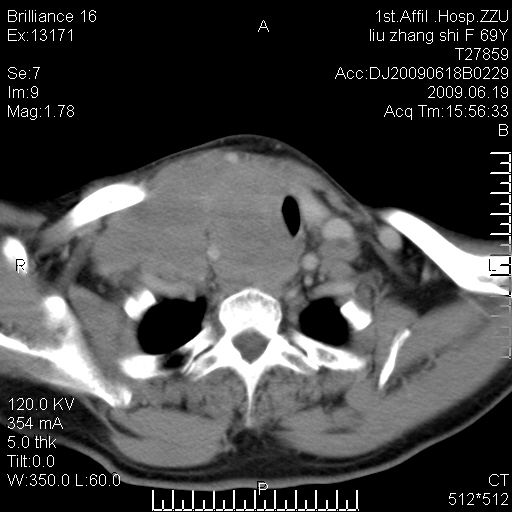

标题: CT26782:女,69岁,颈部占位,3天后公布病理结果。

【病理证实系列】女,69岁,颈部占位,有病理结果,3天后公布。(由于病例时间较久,临床资料不全,请网友见谅)本系列将有几百种常见、少见及罕见病例,均经病理证实。病例资料来自郑州大学第一附属医院。与网友共享,本人有空就发。

甲状腺癌并颈部淋巴结转移。感谢楼主的良苦用心,谢谢。

甲状腺癌并颈部淋巴结转移。

需与鼻咽癌鉴别!

支持甲状腺癌广泛侵及周围结构并颈部淋巴结转移。

鉴别:淋巴瘤、恶性神经源性病变、恶性纤维组织细胞瘤。

病理结果:颈部非霍奇金淋巴瘤。

右侧甲状腺确实有问题